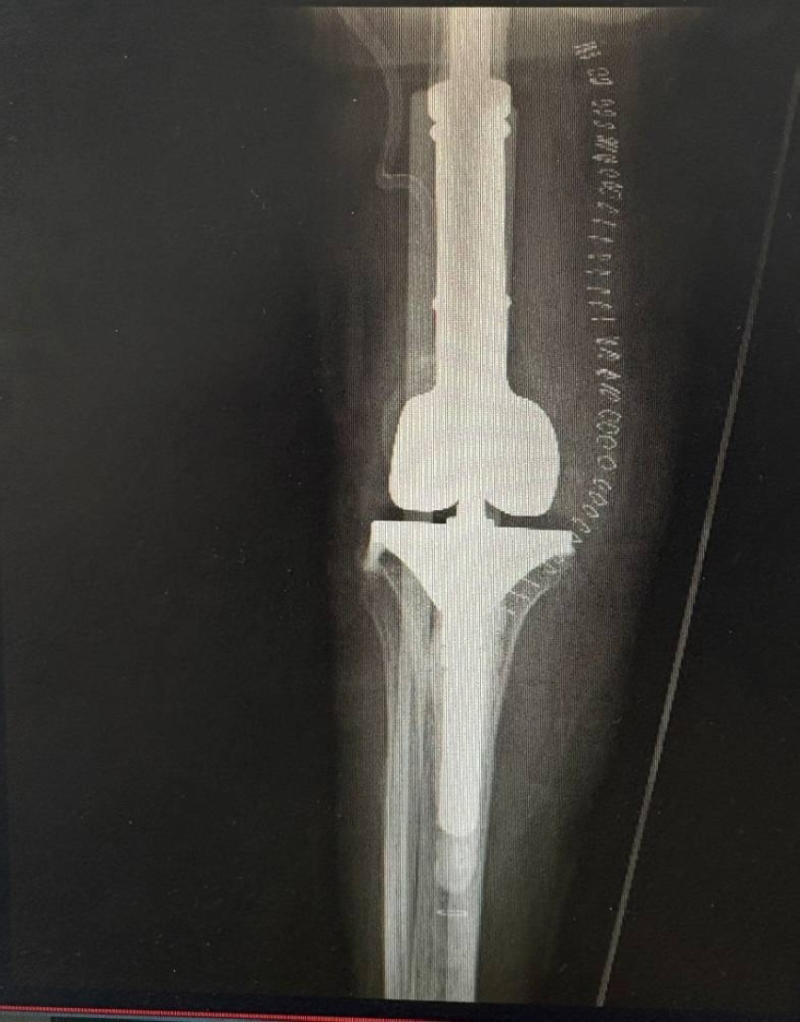

وأوضح التجمع أنه وبعد دراسة الحالة بشكلٍ مكثف، ومناقشة الخيارات العلاجية المناسبة، تقرر إجراء عملية استبدال الجزء البعيد من عظمة الفخذ مع تغيير مفصل الركبة (Distal Femur Replacement)، وهي من العمليات التخصصية الدقيقة التي تُجرى للحالات المعقدة، وتتطلب مستوىً عاليًا من الخبرة والدقة في.....